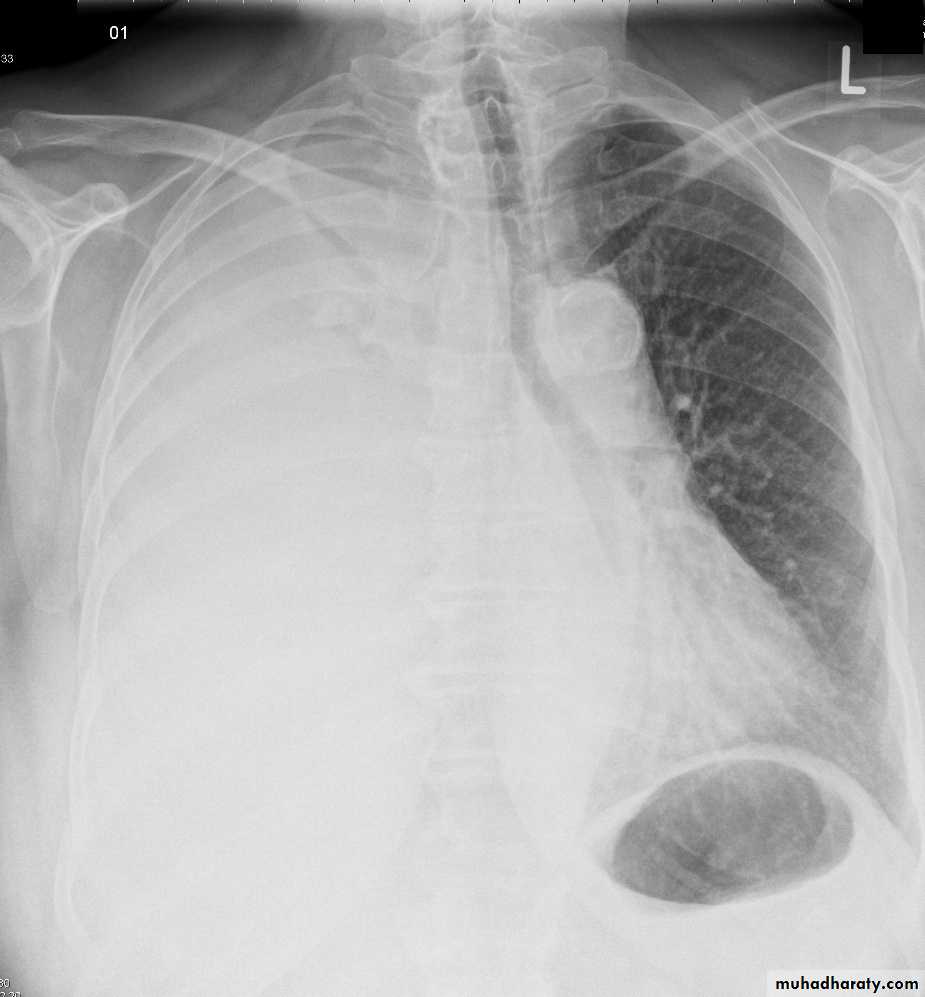

48.opasified hemi thorax

49.total collapse

Total collapse total consolidation

Total collapse